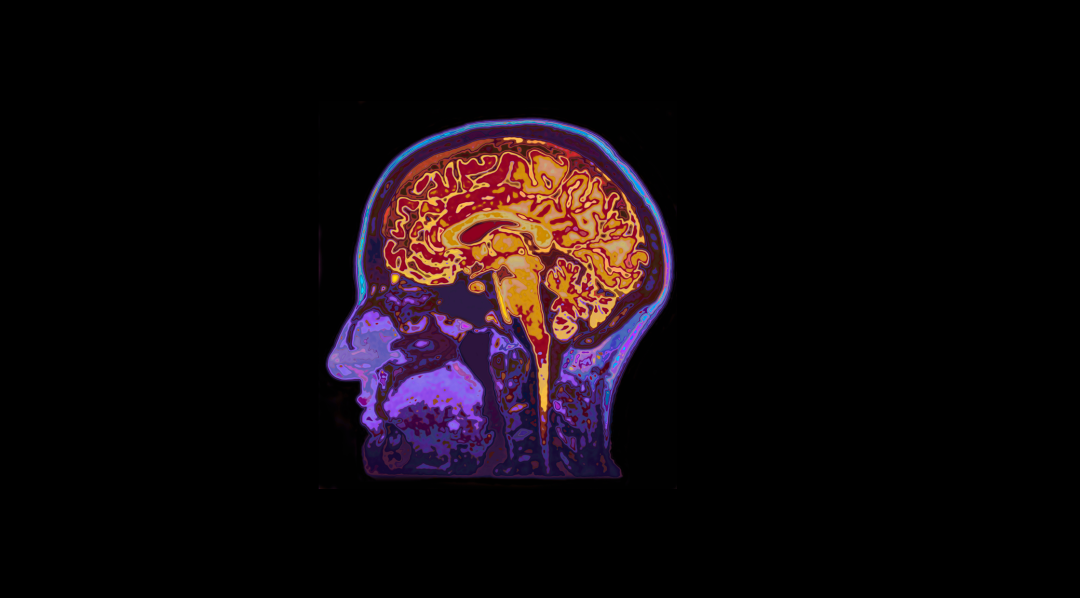

他们发现,睡眠不足会对6-12岁青少年的神经认知发育产生长期的不利影响,而皮质–基底节的功能连接介导了睡眠不足对抑郁、思维问题和晶体智力的影响,前颞叶的结构介导了睡眠不足对晶体智力的影响。

接下来,再跟着研究人员深入大脑,看看睡眠不足如何改变脑功能、脑结构。

总的来说,本研究通过大规模的队列研究,在两年的时间跨度上,发现睡眠不足(少于9小时)对于青少年的行为问题、心理健康、认知以及大脑功能和结构存在持续的不利影响。另一方面,初步探索了大脑功能和结构在介导睡眠不足引起认知和行为变化上的潜在机制,发现皮质-基底节的功能连接介导睡眠不足对抑郁、思维问题和固定智力的影响,而前颞叶的结构则介导睡眠不足对固定智力的影响。